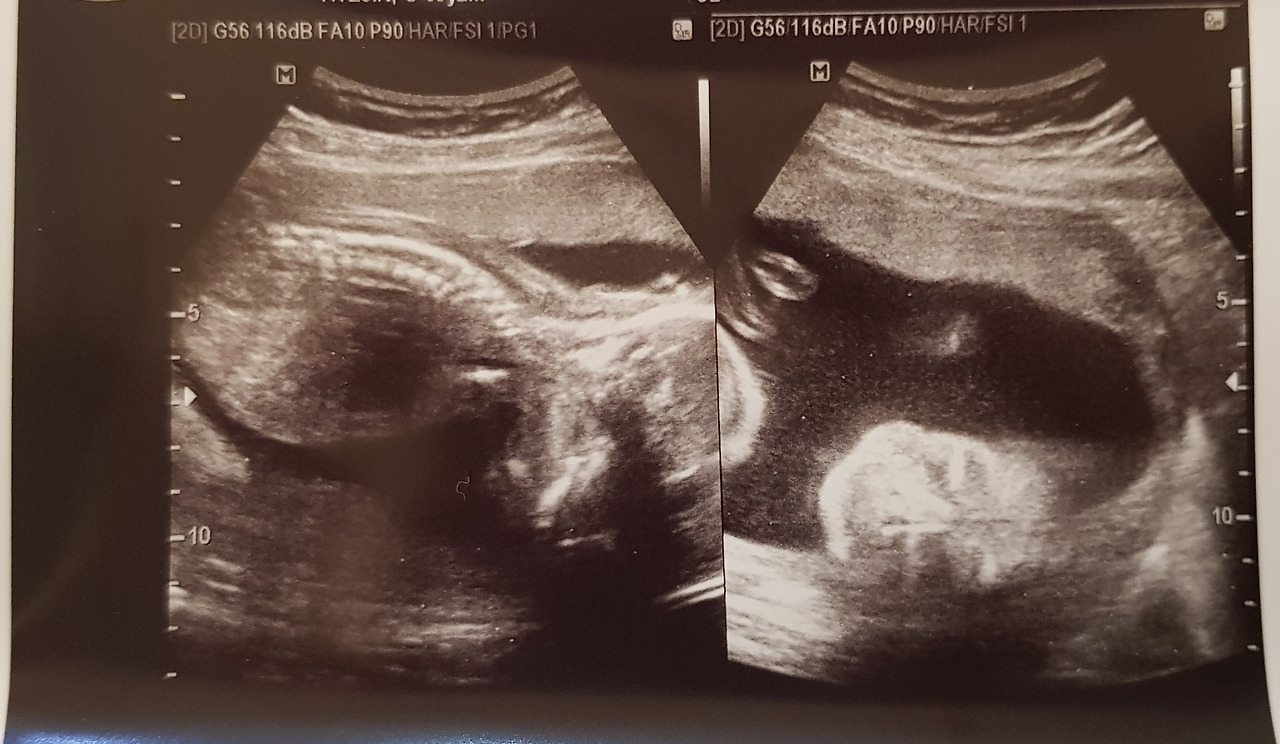

나날이 아빠 붕어빵이 되어가던 시절의 초음파 사진

반짝이는 하루가 다르게 커졌다. 콩만 한 점일 뿐이던 생명체는 이제 팔다리까지 생긴 어엿한 사람의 형체가 되었다. 2주마다 방문하던 산부인과도 20주가 지나 안정기에 접어들자 한 달에 한 번의 방문으로 줄어들었다. 여전히 양치하기는 괴롭지만 그래도 밥을 먹을 수 있을 정도로 입덧이 호전되었고 온 몸을 짓누르던 피로감과 졸음도 사그라졌다. 몸이 덜 힘드니 마음도 따라 여유로워졌다. 어느새 봉곳하게 부분 아랫배가 마냥 기쁘기만 하던 나날이었다.

막상 병원 침대에 누워 기계 너머로 들리는 힘찬 심장 소리와 작은 꼼지락 거림을 보면

그런 것들은 그저, 순식간에 저 먼 어딘가로 사라져 버린다.

점만큼이나 작아져서 아무렇지 않은 일이 된다.

기가 막힌 일이다.

그렇게 즐겁던 글을 못쓰고, 맛있는 것도 못 먹는 데도.

멀쩡하던 몸이 뒤틀리고 휘어지는데도.

그런데도 그것이 순식간에 '별것 아닌 일'이 되어버리는 기적이, 까만 화면 너머에 웅크리고 있다.